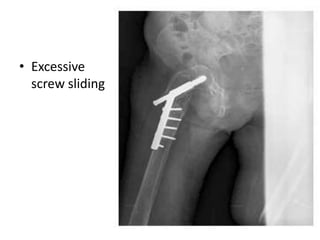

• Excessive

screw sliding